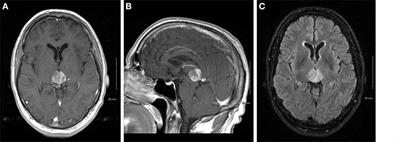

Glioblastoma (GBM) - American Brain Tumor Association Jan 1 20Glioblastoma is a malignant (cancerous) brain tumor that develops from a specific type of brain cell called an astrocyte. Glioblastoma - Glioblastoma is a type of astrocytoma, a cancer that forms from star-shaped cells in the brain called astrocytes. Glioblastoma: Survival Rates, Treatments, and Causes May 1 20Glioblastoma is a type of very aggressive brain tumor. Glioblastoma - Overview - Mayo Clinic Glioblastoma is an aggressive type of cancer that can occur in the brain or spinal cord.

In adults, this cancer usually starts in the cerebrum, the largest part of your. Glioblastoma is one of a group of tumors called astrocytomas. Glioblastoma forms from cells called astrocytes that support nerve cells.